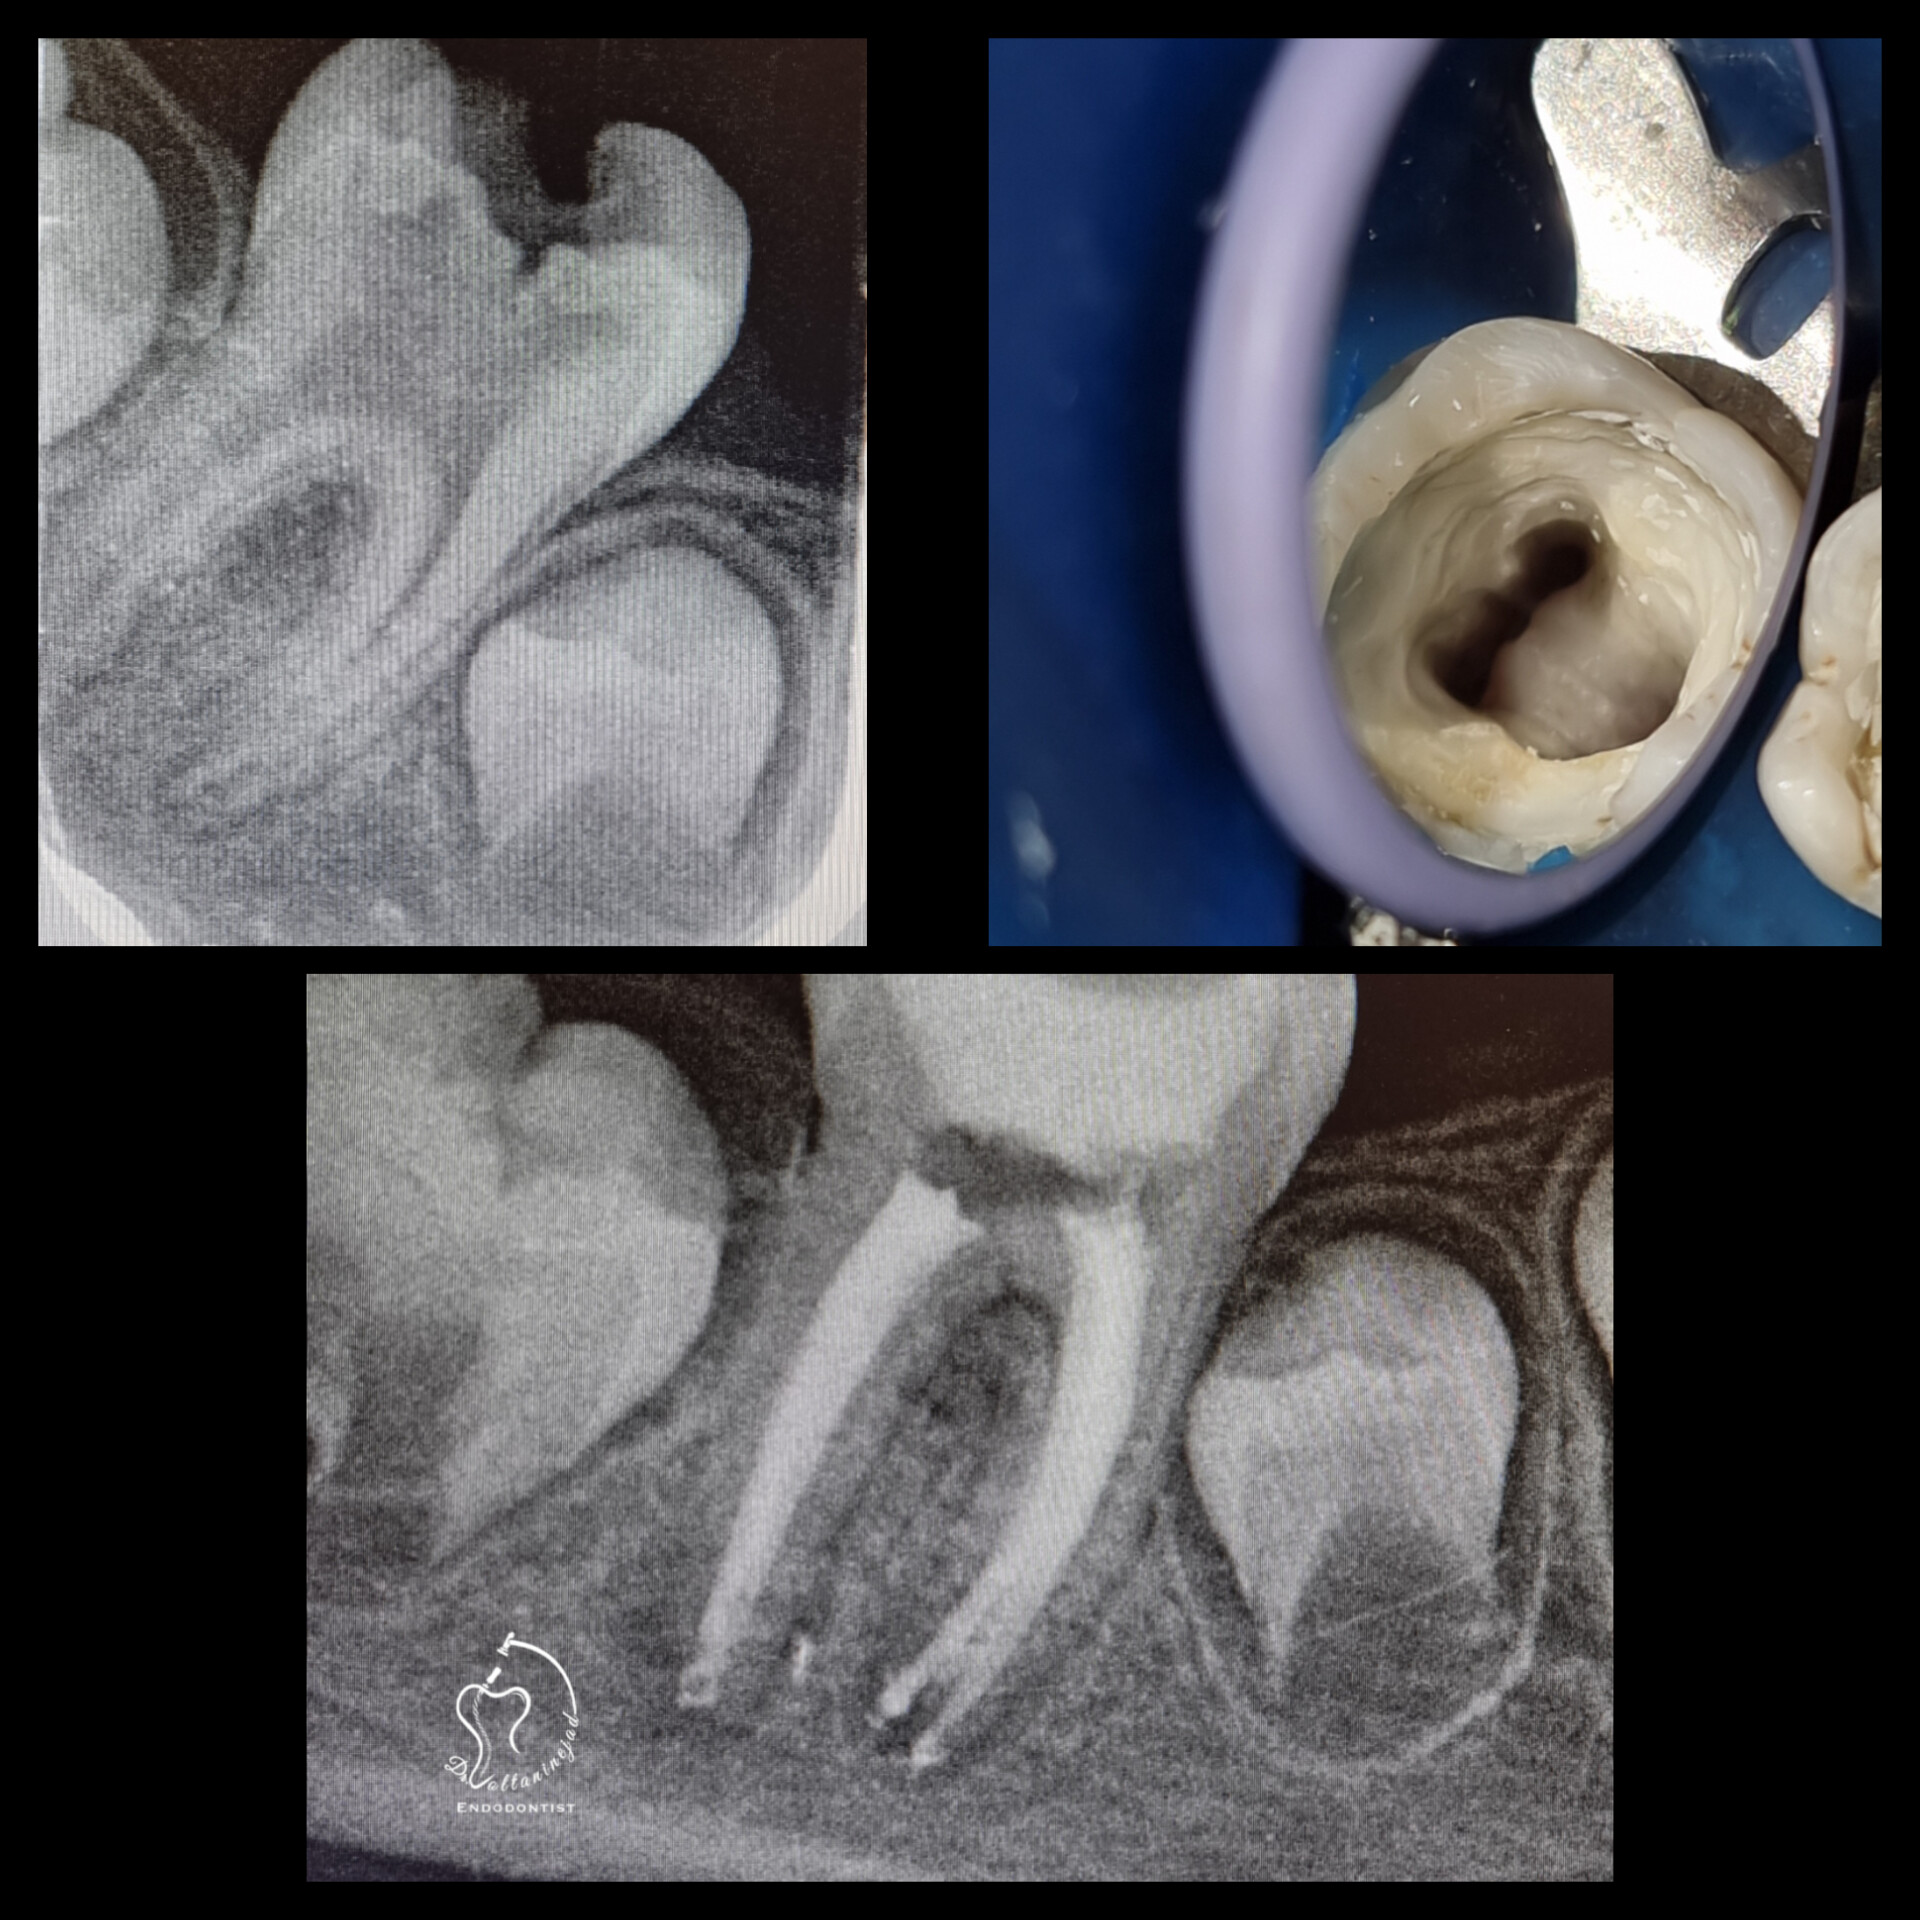

🔹 درمان ریشه دندان دائمی نابالغ با انتهای ریشه باز و آبسه مزمن در کودک ۸ ساله

• شرح کوتاه: کودک ۸ ساله با دندان دائمی نابالغ عفونی و آبسه مزمن مراجعه کرد که درمان ریشه تخصصی میکروسکوپی با موفقیت انجام شد.

• نتیجه: حذف ضایعه مقاوم و حفظ دندان به مدت طولانی.

درمان ریشه دندان نابالغ